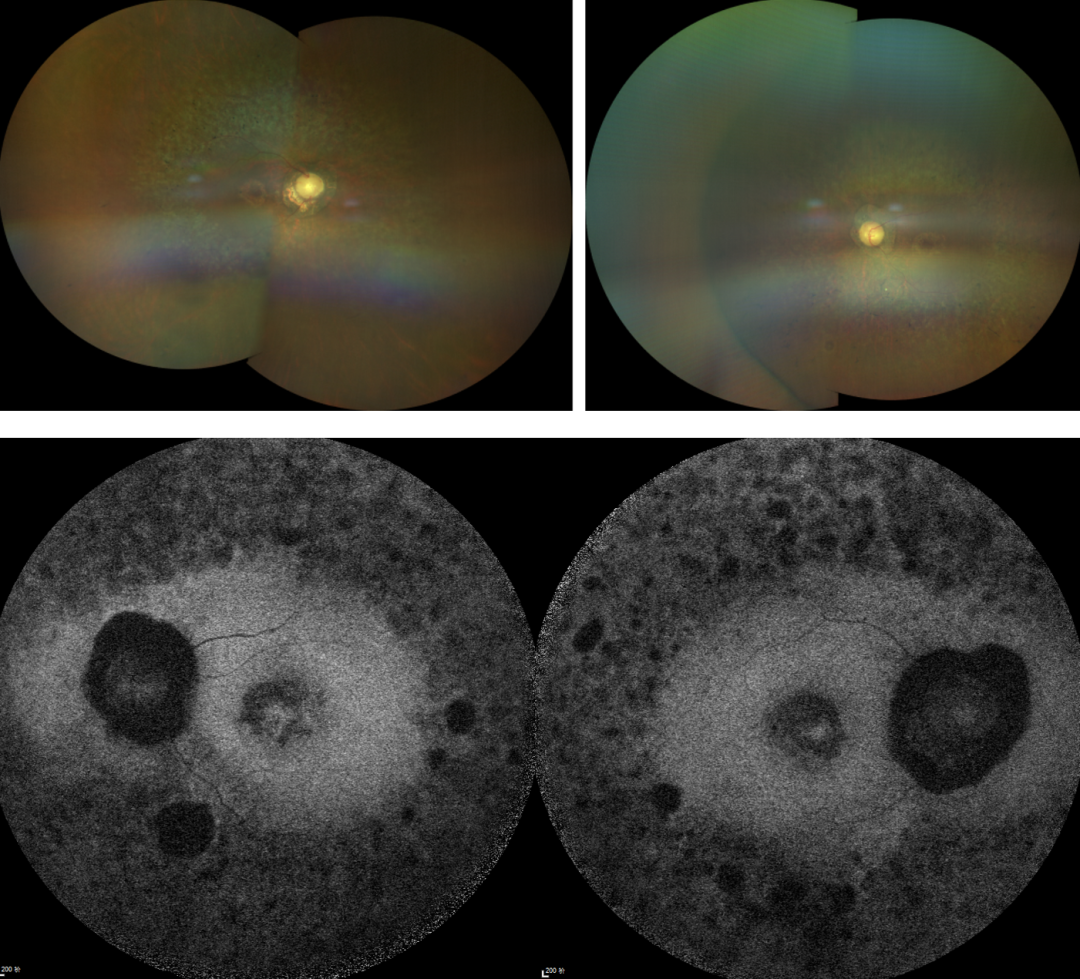

RP的診斷主要依靠眼底檢查、視野檢查、視網膜電圖(ERG)和基因檢測。眼底檢查可見典型的"骨細胞樣"色素沉著,ERG顯示視網膜功能下降,基因檢測可確定具體的突變基因。

視網膜色素變性